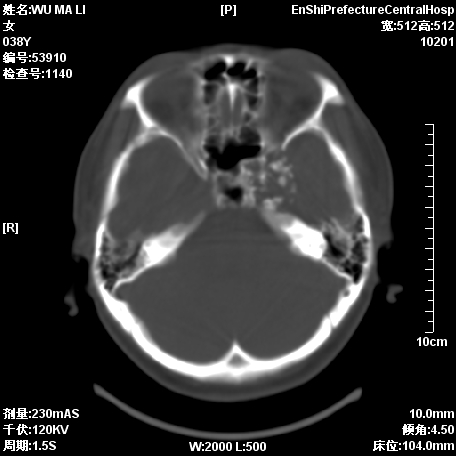

标题: CT11244:颅底病变,请教高手,已行MRI检查,随后发 [打印本页]

患者,38岁,因左侧偏盲月余求治.

补充图片

脊索瘤?脑膜瘤?

图像不全啊,考虑脊索瘤可能性大.

考虑脊索瘤可能性大

考虑脊索瘤可能性

可考虑  脑膜瘤、脊索瘤、软骨瘤

支持脊索瘤诊断

脑膜瘤?脊索瘤?

考虑为:1)脊索瘤。2)软骨瘤?

支持脊索瘤

图像不全,考虑脊索瘤可能性大.

支持考虑:  脑膜瘤、脊索瘤、软骨瘤  。